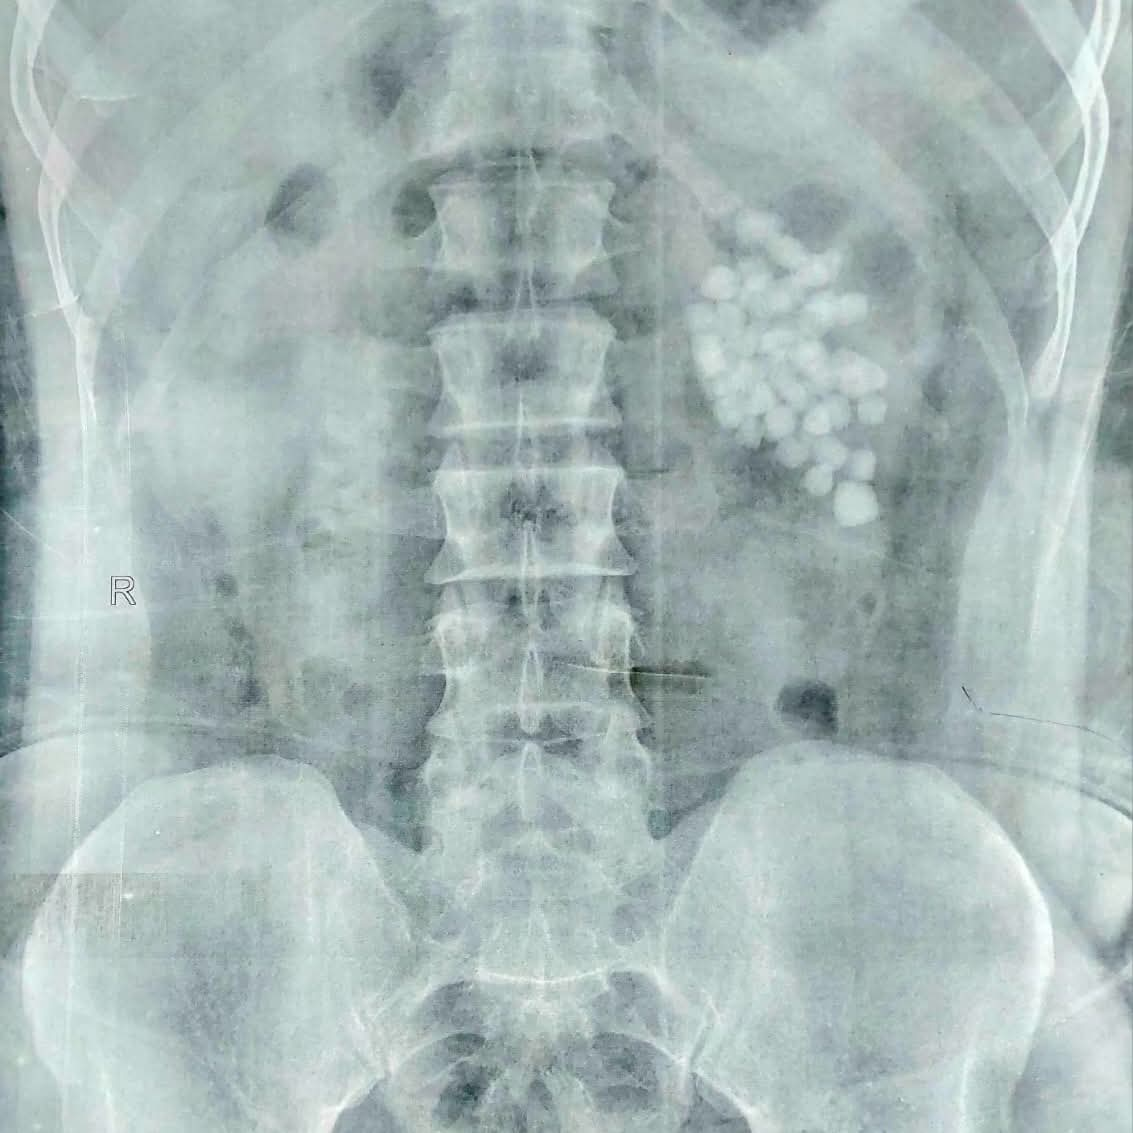

عملية استغرقت ساعتين.. استخراج 58 حصوة من كلية مريض بمستشفى قنا الجامعي

أعلنت مستشفيات قنا الجامعية، نجاح فريق طبي متخصص بمستشفى المعبر الجامعي، في إجراء عملية دقيقة لاستخراج 58 حصوة من الكلية اليسرى لمريض يبلغ من العمر 40 عامًا، وذلك باستخدام أحدث تقنيات مناظير الكلى المتقدمة.

وأوضح الأستاذ الدكتور مصطفى عبد الرازق رئيس قسم المسالك البولية، أن المريض وصل وهو يعاني من آلام متكررة وارتفاع في نسبة الأملاح، وبفحصه تبيّن وجود عدد كبير من الحصوات المتجمعة في حوض الكلية اليسرى، ما استدعى التدخل الجراحي حفاظًا على وظائف الكلية.